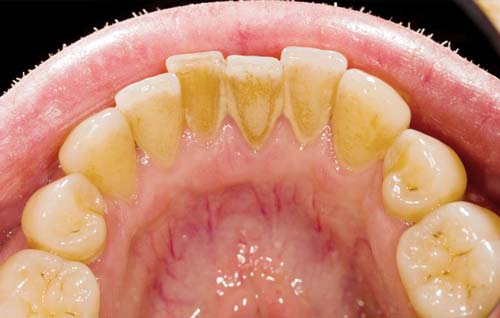

تصویر پایین نیز عکسی است که از همین دهان پیش از تمیز کردن حرفه ای دهان گرفته شده است.

جرم در هر گونه سطح دندانی و حتی زیر خط لثه تشکیل میشود. یکی از سطوحی که جرم به راحتی در آن پنهان میشود سطح پشتی دندانهای جلویی فک پایین است. غدد بزاق زیر زبان، کلسیم زیادی منتشر میکنند که به پلاکها کمک میکند سریعتر سخت شوند.

اگر دوباره به تصاویر بالا نگاه کنید، میبینید که لثه های بیمار دچار پسروی شده اند که علت آن تحریک و التهاب ناشی از رسوب و جرمهای موجود در سطح دندان است.